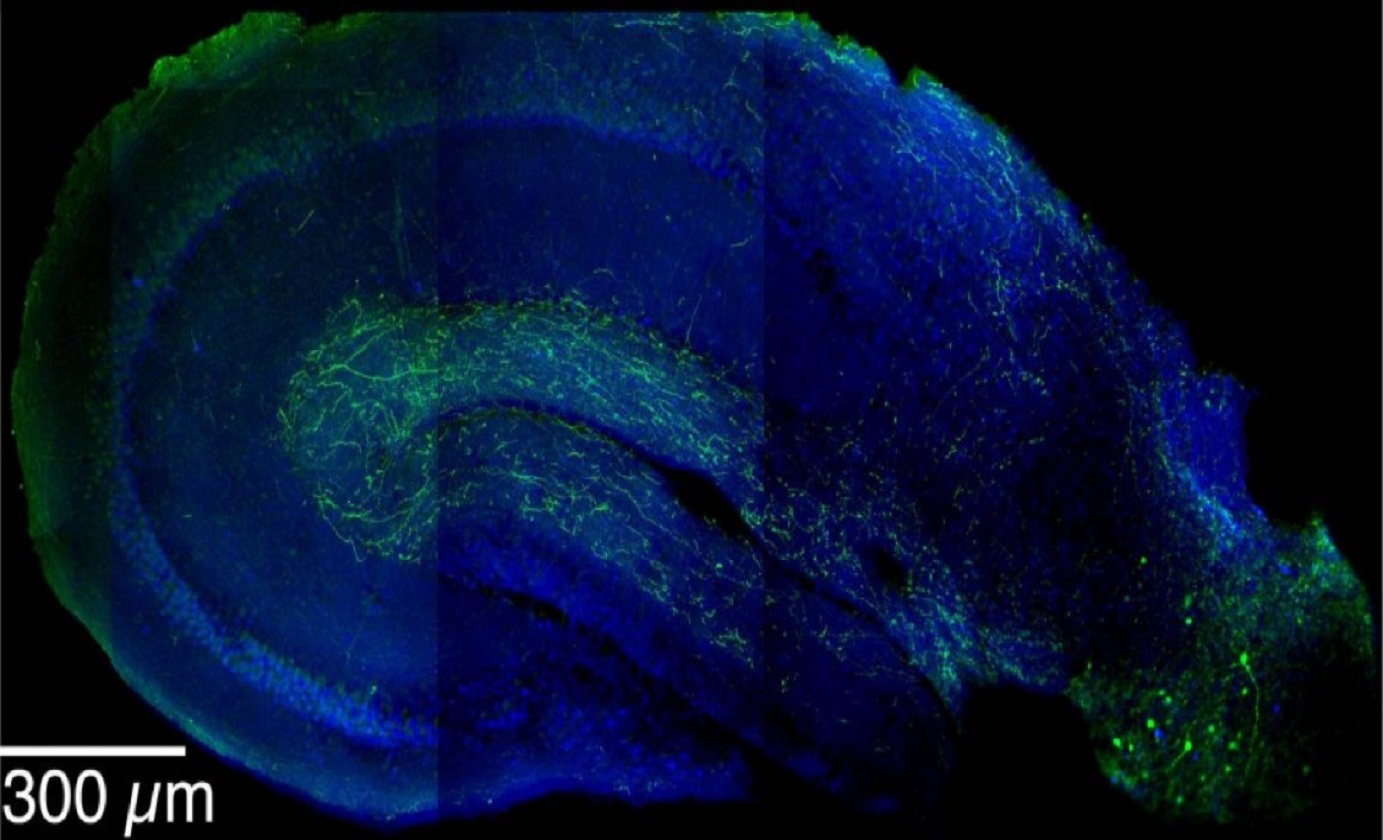

Imagen que muestra las neuronas inhibitorias LRIPs (en verde) extendiéndose desde la corteza entorrinal (en la parte inferior derecha) hacia el hipocampo. Se ha descubierto que las LRIPs forman parte de un sofisticado mecanismo crítico en la formación de recuerdos de contexto. Imagen: Jayeeta Basu. Fuente: Mortimer B. Zuckerman Mind Brain Behavior Institute.

En este caso, el circuito se halló en dos regiones cerebrales interconectadas: el hipocampo y la corteza entorrinal, ambas implicadas en la memoria y en la orientación. Hasta ahora, se sabía que estas áreas se conectaban siguiendo dos vías para formar memorias “de contexto”; pero había una tercera vía de conexión entre ellas cuya función permanecía sin aclarar.

En la tercera vía de conexión entre el hipocampo y la corteza entorrinal mencionada, sin embargo, las neuronas funcionan de manera algo extraña: son inhibitorias, pero a través de una distancia relativamente larga. Por eso, estas neuronas han recibido el nombre de proyecciones inhibitorias de largo alcance o LRIPs.

En este caso, el circuito se halló en dos regiones cerebrales interconectadas: el hipocampo y la corteza entorrinal, ambas implicadas en la memoria y en la orientación. Hasta ahora, se sabía que estas áreas se conectaban siguiendo dos vías para formar memorias “de contexto”; pero había una tercera vía de conexión entre ellas cuya función permanecía sin aclarar.

En la tercera vía de conexión entre el hipocampo y la corteza entorrinal mencionada, sin embargo, las neuronas funcionan de manera algo extraña: son inhibitorias, pero a través de una distancia relativamente larga. Por eso, estas neuronas han recibido el nombre de proyecciones inhibitorias de largo alcance o LRIPs.